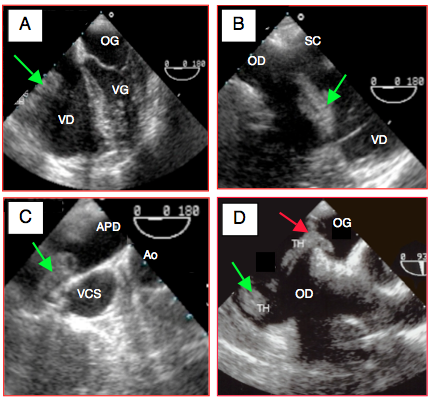

Les principales pathologies rencontrées en urgences sont l’ischémie coronarienne et ses complications (voir Complications de l’ischémie), l’insuffisance mitrale et aortique aiguës sur rupture de l’appareil sous-valvulaire ou sur endocardite (voir Chapitre 26, Endocardite), la dissection aortique et la rupture d’anévrysme thoracique (voir Dissection, Anévrysme et Traumatisme aortique), la tamponnade (voir Tamponnade), l'assistance circulatoire (voir Chapitre 12, Assistance ventriculaire), l'arrêt cardiaque, la transplantation, le traumatisme thoracique et l’embolie pulmonaire. Nous n’aborderons ici que ces trois derniers sujets. La plupart des autres situations sont traitées au Chapitre 25, Instabilité hémodynamique. En plus de cette liste, l’ETO est extrêmement utile pour le diagnostic différentiel et la gestion de toutes les instabilités hémodynamique sévères ou inexpliquées.